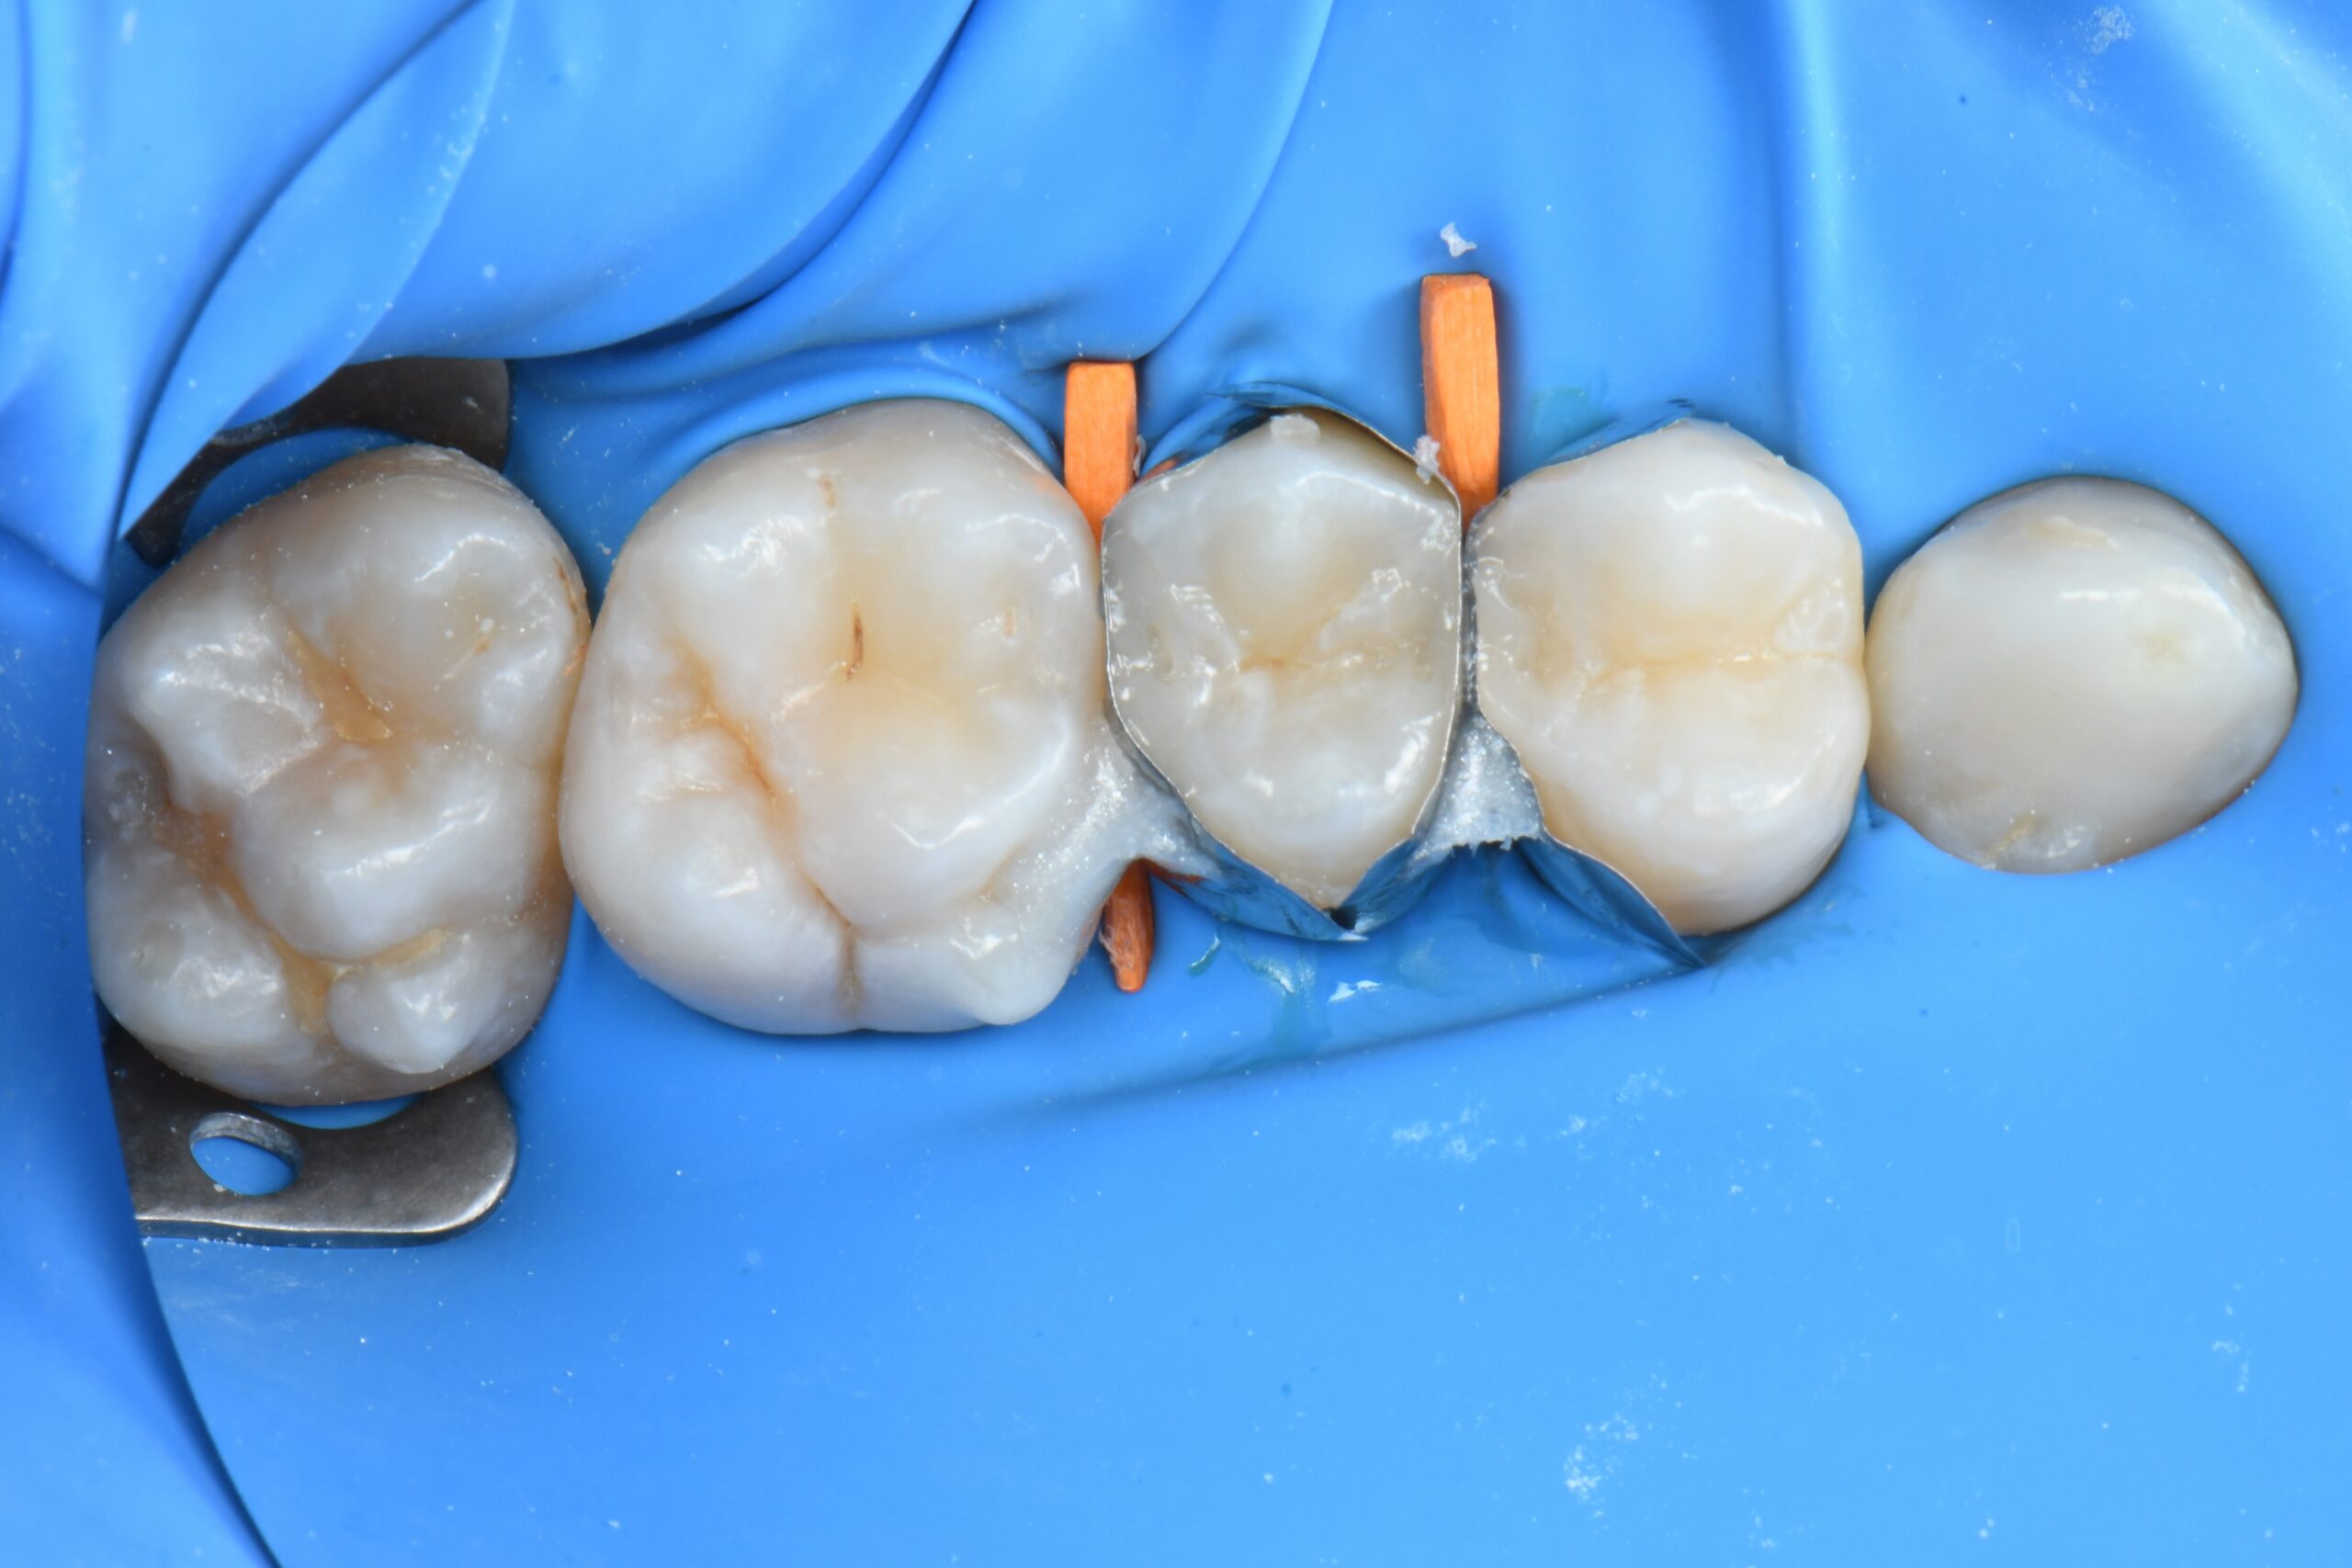

Close-up of molar teeth with dental matrix bands and wedges in place for restorative treatment

Sectional matrices, wedges and rings are properly placed, and selective enamel etching is performed.

Close-up of four molar teeth isolated with a blue dental dam and separated by orange wedges

The residual cavity in the premolar is filled and occlusal anatomy is shaped.